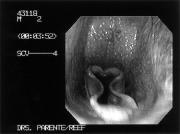

The horse's pharyngeal and laryngeal function is continuously monitored with a state-of-the-art videoendoscope. The scope allows the image to be seen in exquisite detail in full color on a 20-inch monitor, as well as recorded on standard videotape. Photographs of any abnormalities that are found can be made from the videotape for the owner, trainer, veterinarian, and the medical record. After the examination, the videotape can be scrutinized in super slow motion, frame-byframe, to detect even the most subtle abnormality.

The most common problems, such as roaring and choking down caused by intermittent dorsal displacement of the soft palate, can usually be easily confirmed. Anumber of other problems which absolutely cannot be diagnosed without a high-speed treadmill evaluation have also been identified. One of these, termed axial deviation of the aryepiglottic folds (ADAF), results in severe narrowing of the airway just in front of the opening to the flaps, every time the horse takes a breath (Figures 1A and 1B). Dynamic collapse of this tissue into the airway usually causes the horse to make an abnormal respiratory noise and to tire during strenuous exercise. This problem has been diagnosed most commonly in Thoroughbred racehorses (80%) but has also been identified in Standardbred (13%) and in Arabian (7%) racehorses. Laser removal of this apparently flaccid or redundant tissue causing the problem usually can be done safely on the standing awake horse on a same-day outpatient basis. Dr. Eric Tulleners, Chief of Surgery at New Bolton Center, who developed the “no-touch” technique, performs the surgery using a 600µouter diameter laser fiber through the hollow channel in the videoendoscope with the image of the horse’s throat projected on a color monitor. The surgery is done with the horse sedated and the throat numbed with a topical anesthetic. As in arthroscopic surgery, traction on the tissue to be removed is necessary. Traction is placed using custom-designed long grasping forceps introduced up the horse’s other nostril. The laser quickly and efficiently cuts tissue and coagulates blood vessels. Bleeding is usually negligible. Anti-inflammatory medication is given after the surgery. Horses are typically restricted to shedrow exercise or small paddock turnout for two weeks

Figure 1A Figure 1B

after surgery to allow for complete healing of this delicate area.

The results of a study of this problem were presented by Dr. Dana King, a surgery resident working with Dr. Tulleners at New Bolton Center, at the 1997 annual Scientific Meeting of the American College of Veterinary Surgeons in Orlando, Florida. Dr. King reported that complications were not encountered, and healing was uniformly unremarkable. Laser surgery definitely improved racing performance on 73% of racehorses and eliminated noise in 75% of horses. In comparison, horses with ADAF that did not undergo surgery and that were rested for less than two months usually did not improve in racing performance when training was resumed.

As an example, ADAF was diagnosed in a talented horse who was the winner of multiple races and had earnings in excess of $400,000. The trainer recognized a breathing problem after the horse atypically performed poorly in a race. Working carefully with the local track veterinarian, they were able to localize the problem to the throat region, but could not pinpoint the exact site. Ahighspeed treadmill evaluation at New Bolton Center performed by Dr. Eric Parente, a member of the Section of Sports Medicine and Imaging, confirmed the problem of ADAF. Standing laser surgery was performed to correct the problem, and the horse convalesced without complications. In the first start back the horse was back to usual form, winning handily.